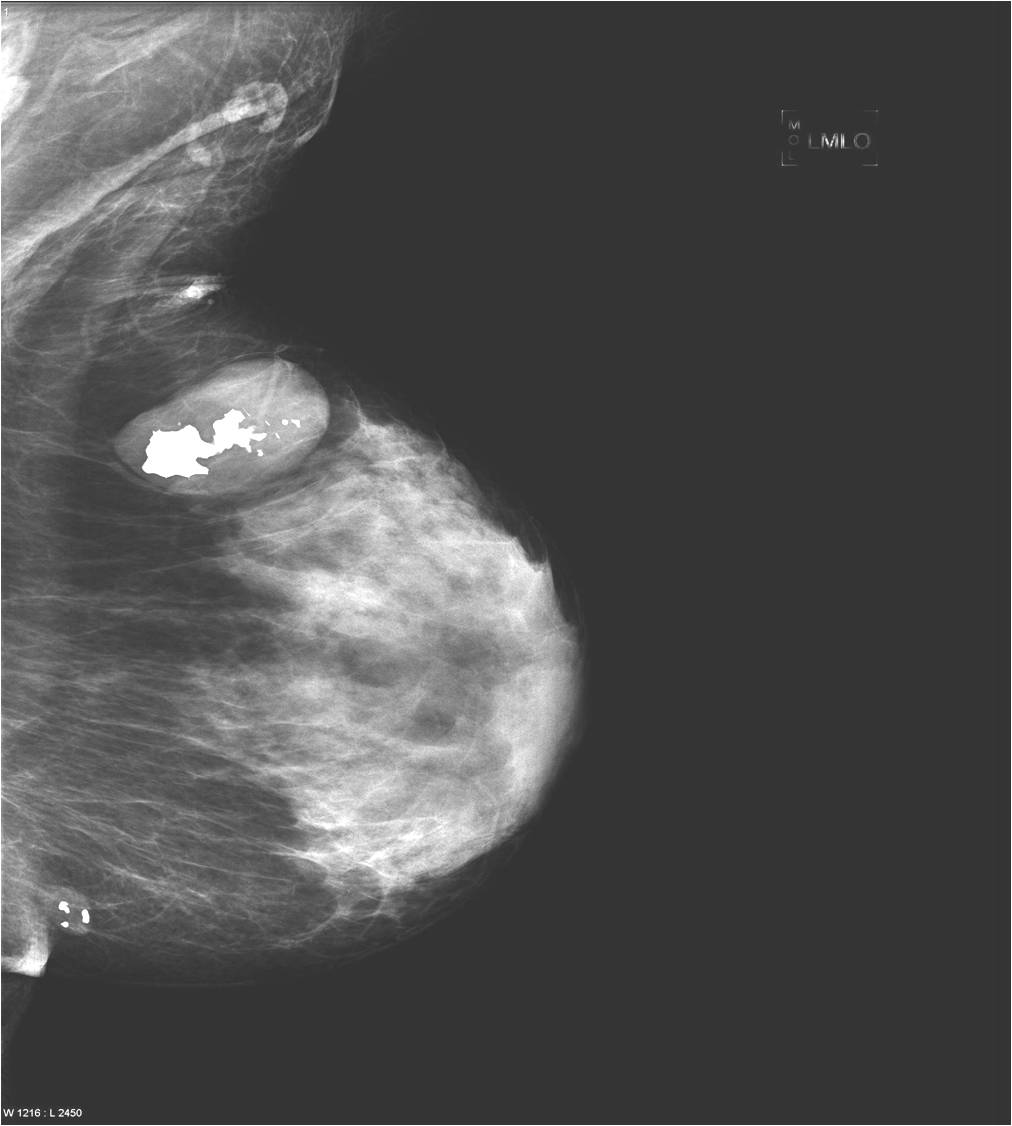

Calcifications are encountered in the breast quite often. Most of them accompany benign process (Picture 21.) and only a smaller percentage actually indicates malignancy. These malignant signs are basically always micro-calcifications. They are ill-shaped, with various pleomorphism (Pictures 23.,24.) and they are usually show a clustered arrangement. Their number is irrelevant to the grade of malignancy. Their analysis with mammography is often hard, but targeted and magnified images can help in it. In most the cases these lesion can’t be identified with ultrasound, so stereotaxy core biopsy is needed.

Image

Picture 23.